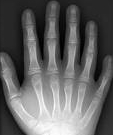

다지증에 걸린 사람의 손 X-ray 사진 예시

- 사지 : 불균등하고 짧은 사지(말단부가 더 심함), 다지증(특히 새끼손가락 옆에 손가락이 더 있음), 짧고 평평한 중지절, 지절 말단의 형성 부전(2~5번째 손가락 끝이 옥수수 형태임), 외반슬이 동반된 경골 상부 측면의 형성 부전, 만곡족

연골외배엽 이형성증은 특징적인 임상 증상으로 진단할 수 있습니다. 방사선 촬영을 통해 사지, 흉곽, 골반의 기형을 확인할 수 있습니다. 또한 ECV와 ECV2 유전자에 대한 돌연변이 검사로 유전적 진단을 할 수 있습니다.